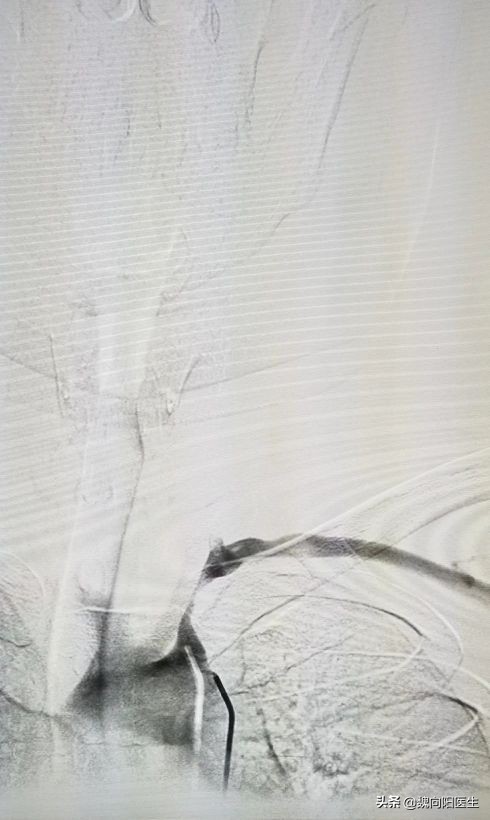

主动脉夹层

动脉夹层是指由于内膜局部撕裂,受到强有力的血液冲击,内膜逐步剥离、扩展,在动脉内形成真、假两腔,从而导致一系列包括撕裂样疼痛的症状体现。

主动脉是身体的主干血管(升主动脉,降主动的和腹主动脉),承受直接来自心脏跳动的压力,血流量巨大,一旦出现内膜层撕裂,若不及时、恰当治疗,破裂的机会非常大,死亡率也非常 高。

主动脉夹层累及锁骨下动脉开口或头臂干开口时会引起相应血管的血流不通畅,从而导致血压测量不准。